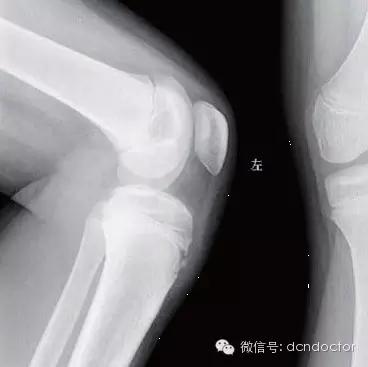

在影像学上的表现主要有:

1.局部软组织肿胀为重要的基本征象,尤其以髌韧带的增大或增厚最为显著,以后肌腱可产生继发性钙化或骨化。

2.胫骨结节骨骺不规则增大,密度不匀,有节裂或边缘光滑的游离骨块。